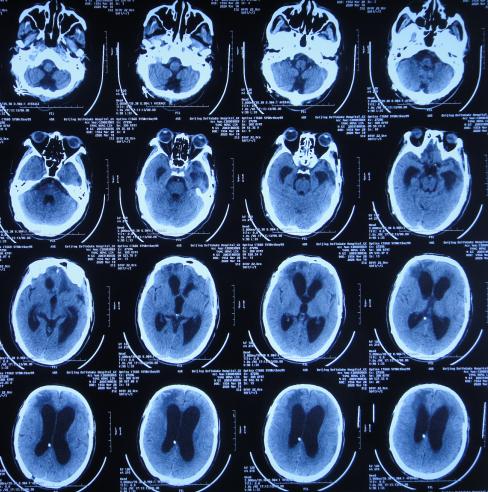

2020年3月18日(颅脑外伤开颅术后149天即颅骨修补术后95天即第2次脑室腹腔分流术后62天,先后经4家医院治疗后仍意识模糊,大小便*禁失**,脑积水,间断发热近2月)转住入李小勇脑脊液科。入院时:意识模糊,大小便*禁失**,体重较前明显减轻,体温高38度左右;头部可见引流管走向;右侧肢体活动差些;鼻饲流食( 图-30 );入院时头颅CT示颅骨修补术后、脑室引流术后仍脑积水,有水肿( 图-31 )。

图-30: 2020年3月18日入院时

图-31: 2020年3月18日头颅CT

入院次日拔除了原脑室腹腔分流管+脑室外引流术( 图-32 )。

图-32: 2020年3月19日头颅CT

入院治疗12天即2020年3月30日,查头颅CT示脑室有缩小、水肿有减轻( 图-33 )。

图-33: 2020年3月30日头颅CT

入院治疗19天即2020年4月6日,进行了脑室腹壁外引流术( 图-34 )。